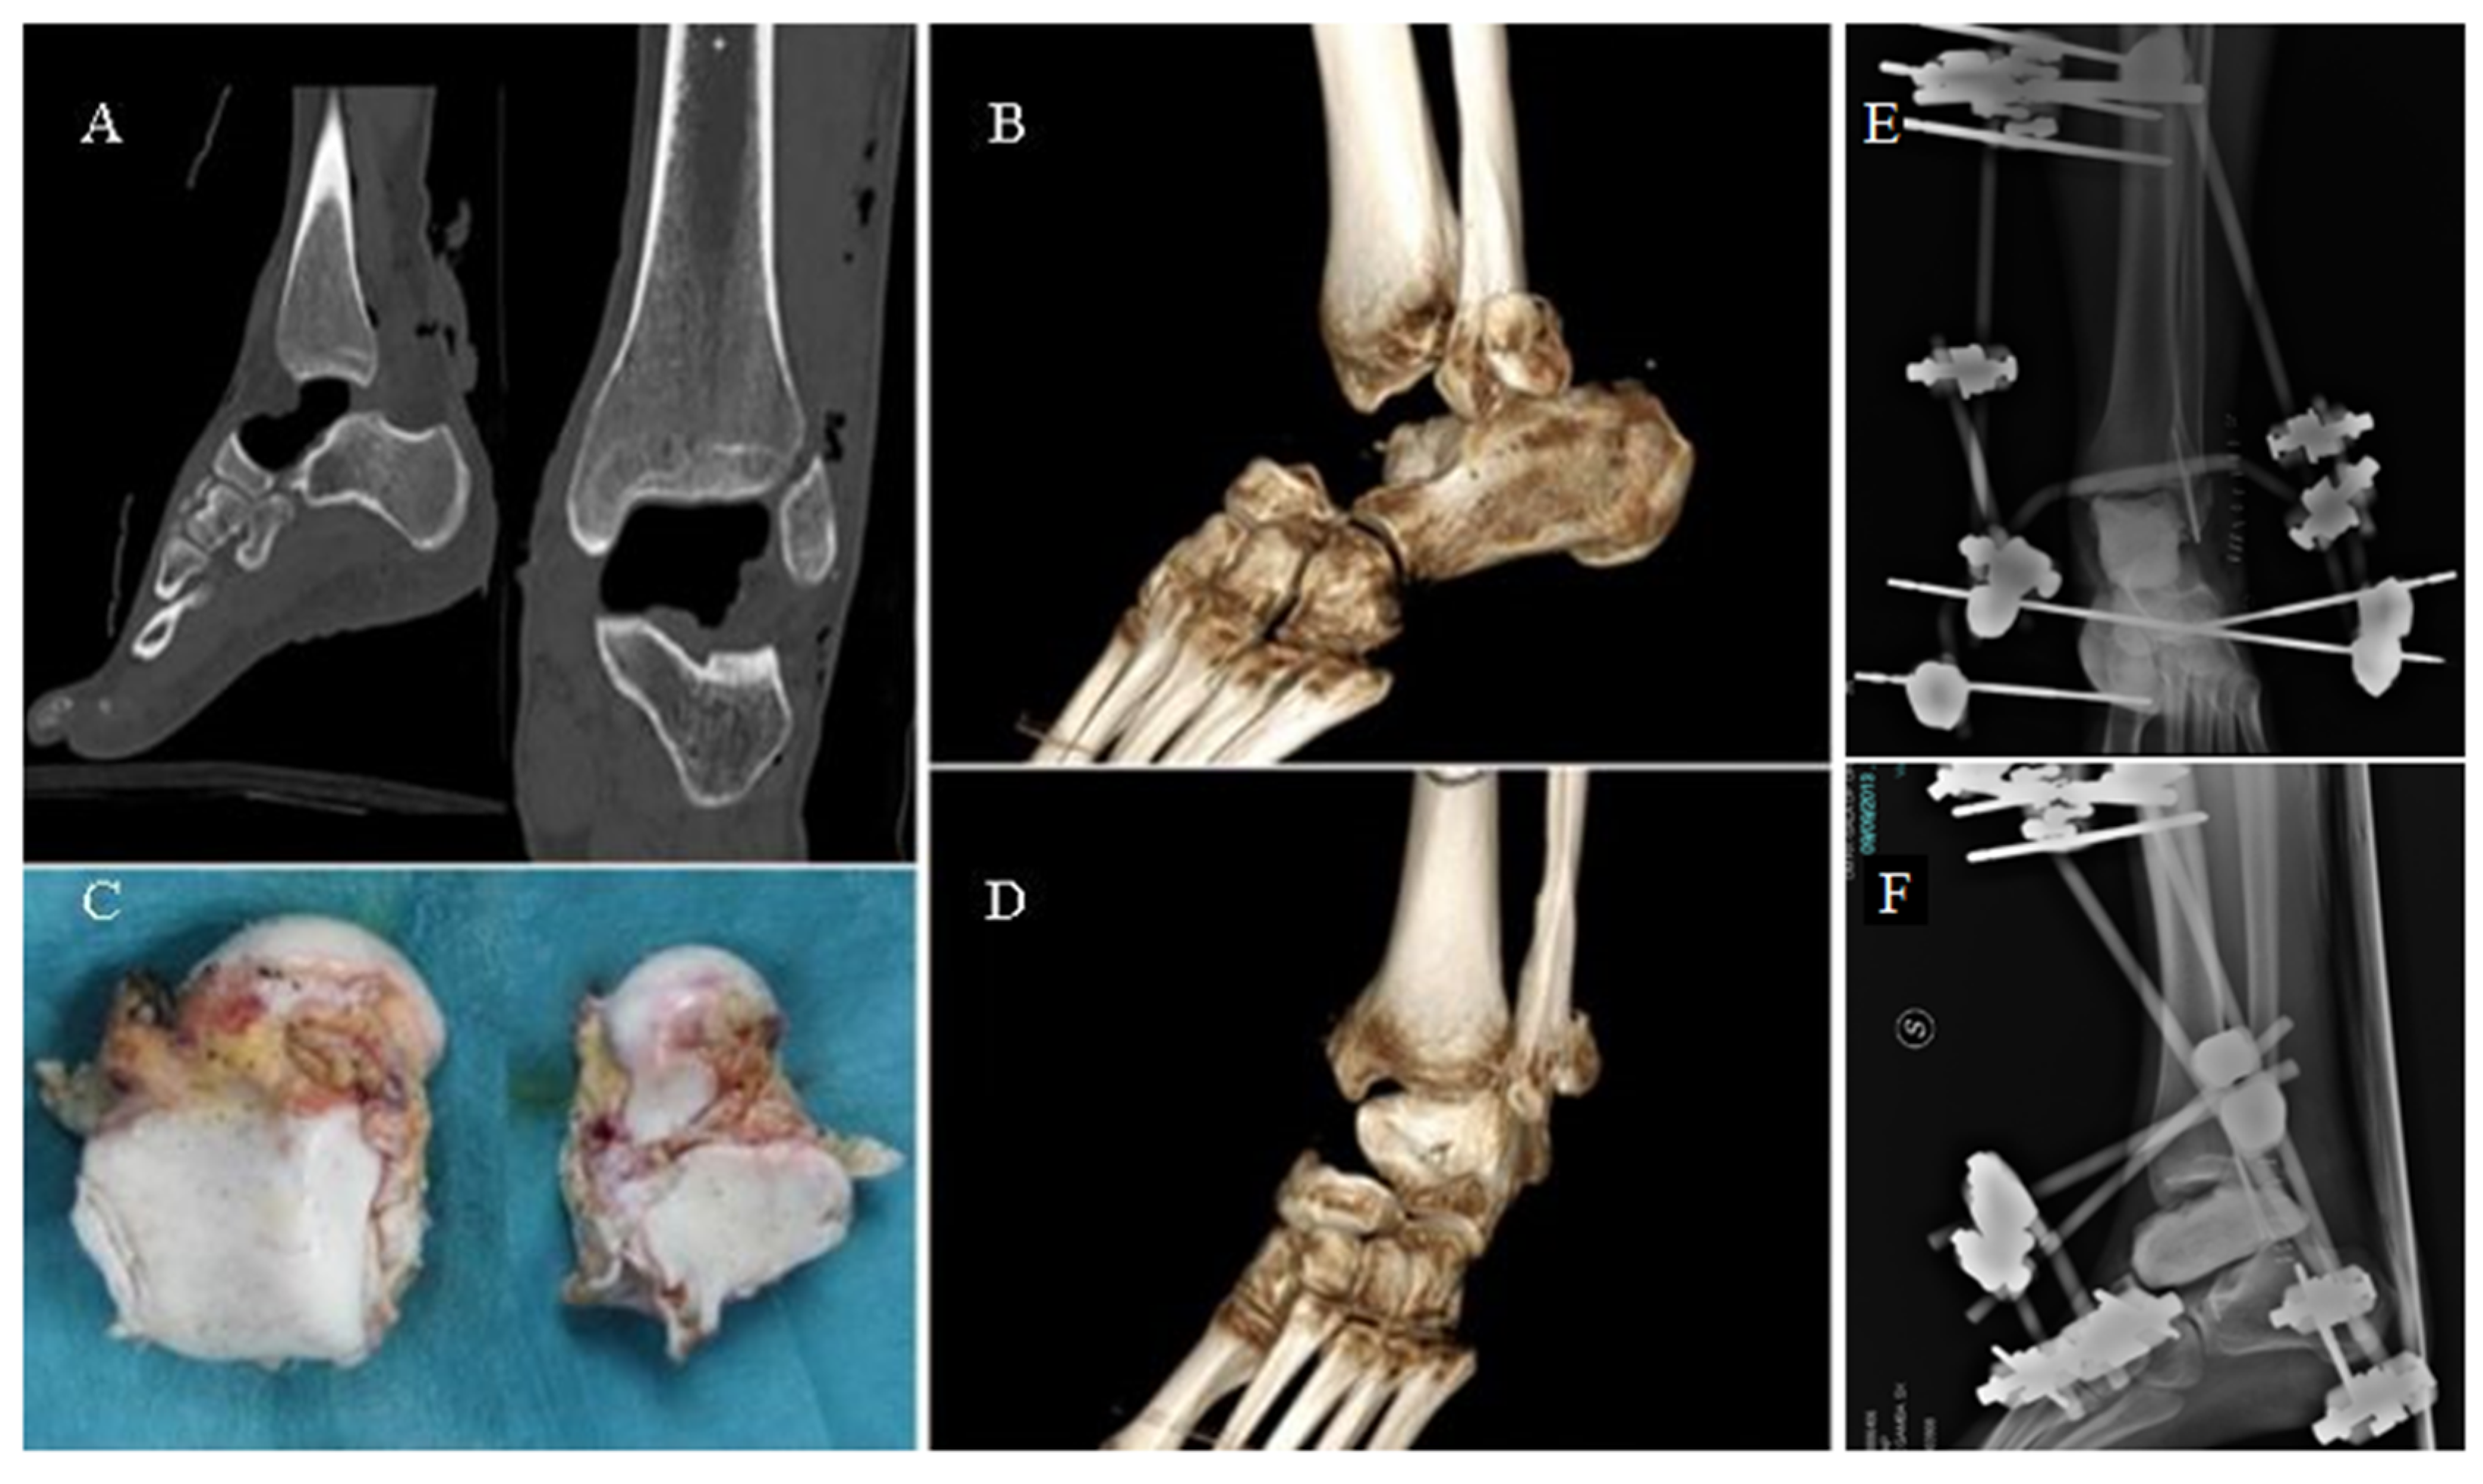

Figure 1.

CT images (A) and volume rendering (B,D) showing the gap left by the talus (C). External fixation of the ankle joint (E,F).

A 27-year-old male patient suffered a road accident in September 2013, reporting a superficial traumatic head injury and a left fibular fracture with an open wound and complete enucleation of the left talus. The missing talus was collected: It presented minor osteochondral injuries in the medial part and macroscopic contamination but was not fractured. After primary care, the wound on the foot and ankle was washed and debrided, and an antibiotic-coated cement spacer was applied to fill the void left by the talar enucleation (Figure 1). The fibula was stabilized using K-wires, and an external fixator was applied to maintain the stability of the ankle. The talar void was filled by a gentamicin/clindamycin-loaded cement spacer (Figure 1).